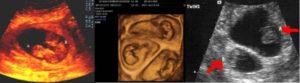

- Ультразвуковое исследование — самый достоверный способ увидеть и определить, какая у женщины беременность, более точный срок беременности, размеры плодов и все патологии, существующие у двоих эмбрионов (если таковые имеются). А также при помощи данного метода возможно определить однояйцевая или разнояйцевая беременность наблюдается у женщины.

Двойню на УЗИ можно увидеть и определить уже на 4-5 неделе беременности. Как правило, однояйцевые близнецы определяются позже, чем разнояйцевые (не раньше 12 недели).

Чтобы определить, многоплодная беременность у будущей мамы или нет, специалист оценивает следующие параметры во время ультразвука:

- число плацент;

- число околоплодных пузырей;

- количество сердцебиений в матке у мамы;

- количество эмбрионов и их размеры.

На раннем сроке шансы увидеть двойню или тройню намного выше, если малыши многояйцевые.

Признаки такие: у каждого из эмбрионов есть отдельная плацента и плодное яйцо, которые легко разглядеть на мониторе.

Если близняшки однояйцевые, у них всегда общая плацента, околоплодные пузыри могут быть разными или общими. В этом случае рассмотреть несколько эмбрионов обычно получается только на 10-12-й неделе.